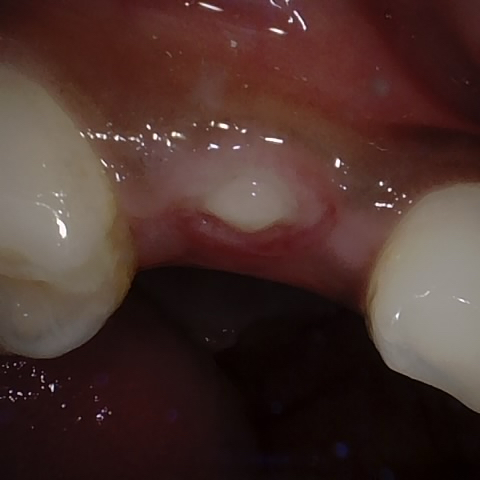

Annotated as "Good"